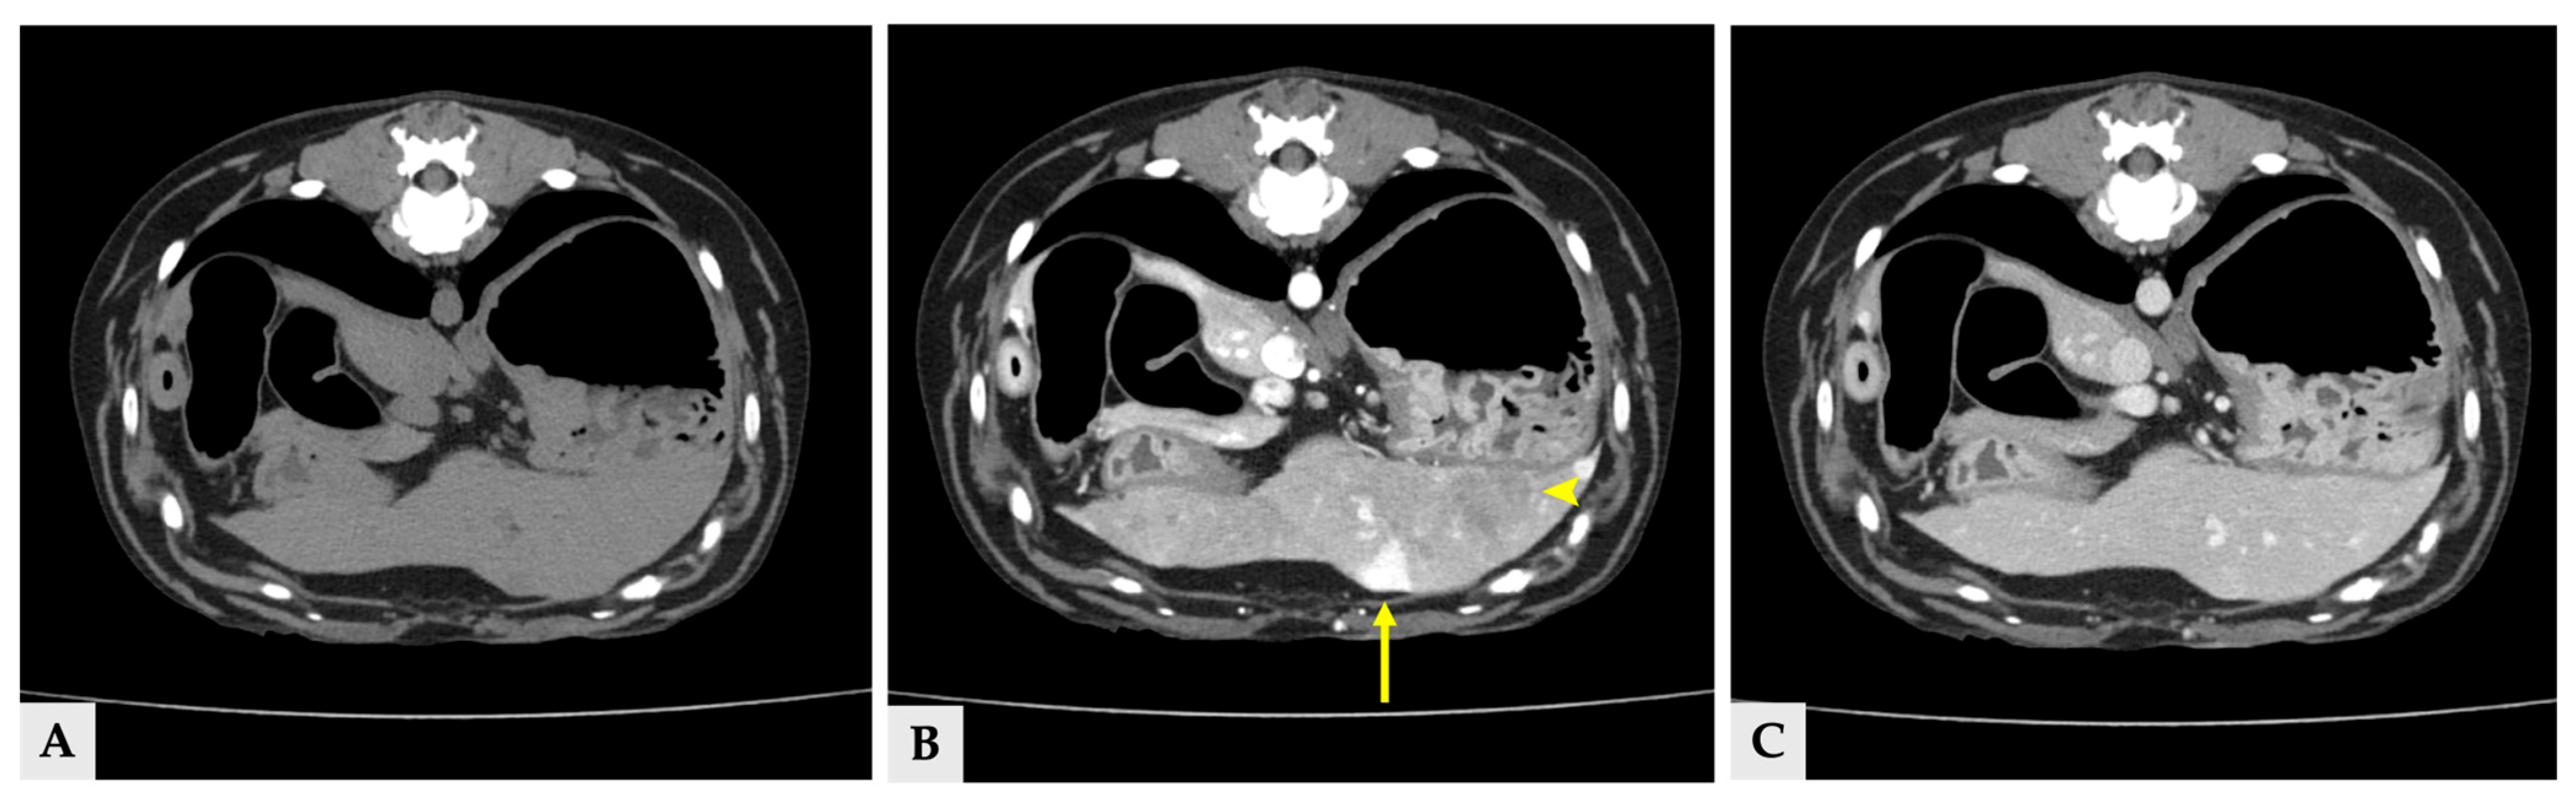

Radiographs demonstrated a soft-tissue opacity over the trachea at the level of C2–C5, causing leftward tracheal deviation (Figure 1). No pulmonary lesions were evident. CT confirmed three well-defined, separate right-sided cervical masses, including the largest palpable cervical mass, extending from the C1 to C5 levels (Figure 2). All three masses were clearly distinct from one another, with no visible continuity on cross-sectional imaging. Mass 1 measured 66.6 mm × 42.0 mm × 37.6 mm (approximately 56 cm3 in volume [14]) and originated from the right thyroid gland. It showed heterogeneous contrast enhancement and produced a filling defect within the adjacent right internal jugular vein, consistent with vascular invasion. Mass 2 measured 25.1 mm × 14.2 mm × 16.5 mm in size, located cranially to mass 1 without any structural connection, and the volume was 3.1 cm3 [14]. Mass 3 measured 11.5 mm × 11.5 mm × 8.6 mm in size, 0.7 cm3 in volume [14] and was positioned between mass 1 and mass2, lying dorsally to mass 2, and was likewise distinctly separated from the other lesions, and the total volume of three masses was approximately 60 cm3 [14]. The left thyroid gland appeared normal, whereas no normal thyroid tissue was identified on the right side at the corresponding anatomical level; instead, only the three masses were present. This finding supports the interpretation that these three lesions originated from the right thyroid gland.

Figure 2.

Delayed phase of CT scan image of three thyroid masses (A–C) transverse view, (D–F) dorsal view. (A,D) Images of right thyroid mass 1, demonstrating a filling effect of right internal jugular vein (arrow). (B,E) Right thyroid mass 2 (arrowhead). (C,F) Right thyroid mass 3, locating between the mass 1 and 2 (asterisk).

No evidence of pulmonary metastasis was identified on CT, and the regional lymph nodes showed normal size and homogeneous contrast enhancement. However, both adrenal glands were enlarged (left: 14.1 mm cranial pole, 9.5 mm caudal pole; right: 9.3 mm cranial pole, 5.7 mm caudal pole) while retaining a normal adrenal waist configuration in ultrasonography and CT scan.